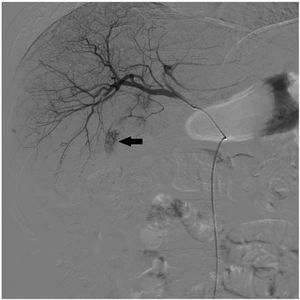

We present the case of a 63-year-old man with liver cirrhosis of mixed aetiology (alcoholic and hepatitis C virus infection) and a diagnosis of a 14-mm hepatocarcinoma in segment III and 40 mm in segment VI. Transarterial chemoembolisation (TACE) of hepatocellular carcinoma was performed by super-selective catheterisation of the feeding arteries of the tumour nodules and they were embolised with doxorubicin (DC-Beads 100−300 μ and 300−500 μ) (Fig. 1). Following the procedure, he developed symptoms consistent with urinary retention, paraesthesia and paresis in both lower limbs with the inability to walk. In the emergency thoracolumbar MRI performed due to suspected spinal cord ischaemia after TACE, an increased signal was observed in the distal portion of the cord and the conus medullaris with moderate restriction in the diffusion sequence (Figs. 2–4), possibly related to an acute ischaemic injury at the level of T11, which was confirmed. Following rehabilitation, the patient was discharged with preserved ambulation.

TACE is based on the almost exclusively arterial vascularisation of the hepatocarcinoma.1 In our patient, the clinical symptoms were accounted for by the existence of an artery feeding the tumour collaterally to one of the spinal arteries that supply the spinal cord, with the chemotherapeutic material entering the spinal cord and inducing unusual transient acute spinal cord ischaemia.